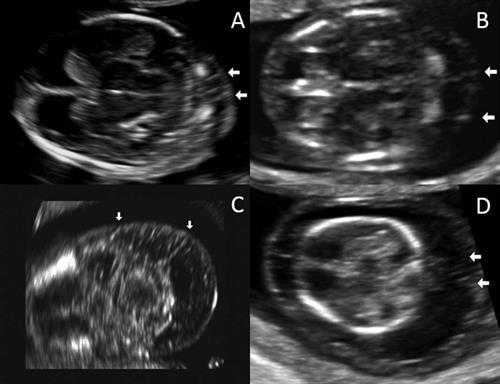

Исследователи ретроспективно просмотрели электронные истории болезни 3275 пациенток, которые проходили скрининг первого триместра и затем рожали в женском отделении Техасского Детского Госпиталя между ноябрем 2011 и декабрем 2014 года. Они характеризовали септы как тонкие линейные эхогенные структуры в воротниковом пространстве плода, которые располагались между кожей плода и нижерасположенными тканями. Кроме того, наличие септ и расширенного воротникового пространства расценивалось как кистозная гигрома.

УЗ изображения воротниковых перегородок в поперечном срезе. А) воротниковое пространство 2.3 мм. В) 4 мм. С) 5.2мм. D) 8мм. Все изображение предоставлены the Journal of Ultrasound in Medicine.

Эти результаты демонстрируют, что визуализация септ воротникового пространства в первом триместре является важным и независимым фактором риска хромосомных аномалий плода, по данным группы исследователей.